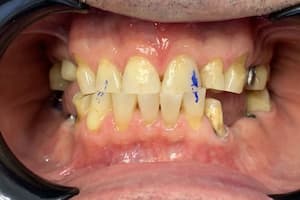

Нерівномірна патологічна стирання зубів, гіперфункції м'язів, відсутність зубів. Відновлення естетики та функціональності зубощелепного ряду верхньої та нижньої щелеп.

Виражений бруксизм, стирання зубів після гнатологічного обстеження лікар вирішив завищувати прикус до 2 мм і фіксацію центрального співвідношення. Встановлено коронки E.max на свої зуби. Коронки на імплантах виготовлені з металокераміки для запобігання сколам.